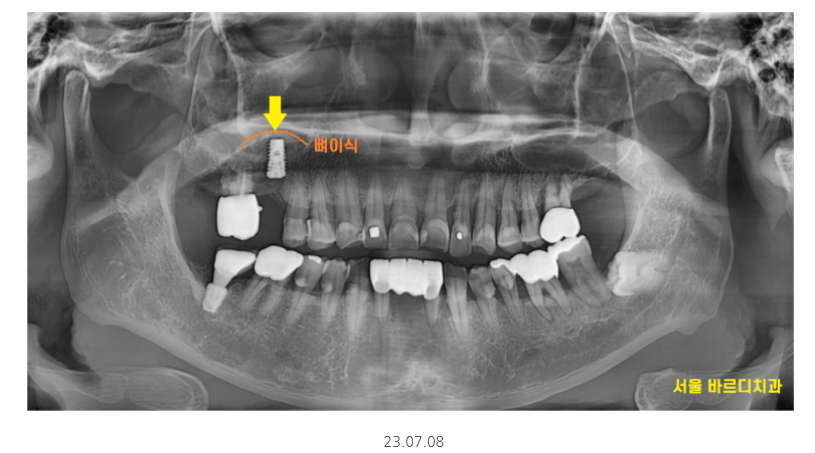

제일 불편을 호소한 치아 한개만 발치 후

임플란트를 진행했습니다.

강일동 임플란트가 완성되기까지

다른 부위 잇몸치료도 진행해드리고

관리해드렸습니다.

한번으로 끝난것이 아니라

3개월에 한번씩 하시기로 하셨는데요.

잇몸은 나빠지면 회복되지 않기에..

임플란트 치료가 끝나도 계속~